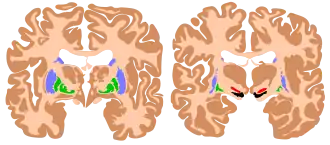

Au sens purement anatomique ils comprennent quatre noyaux pairs :

- le noyau caudé ;

- le noyau lenticulaire correspondant au putamen et au pallidum ;

- le noyau sous-thalamique ;

- la substance noire.

Au sens fonctionnel, on aborde ces structures de manière différente :

- le striatum composé du noyau caudé et du putamen (correspondant à la partie latérale du noyau lenticulaire) ;

- le globus pallidus interne (GPi) et le globus pallidus externe (GPe), correspondant au pallidum (partie médiale du noyau lenticulaire) ;

- le noyau sous-thalamique (ou corps de Luys) ;

- la substance noire compacte (SNpc, du latin : substantia nigra pars compacta), et la substance noire réticulée (SNr, substantia nigra pars reticulata).